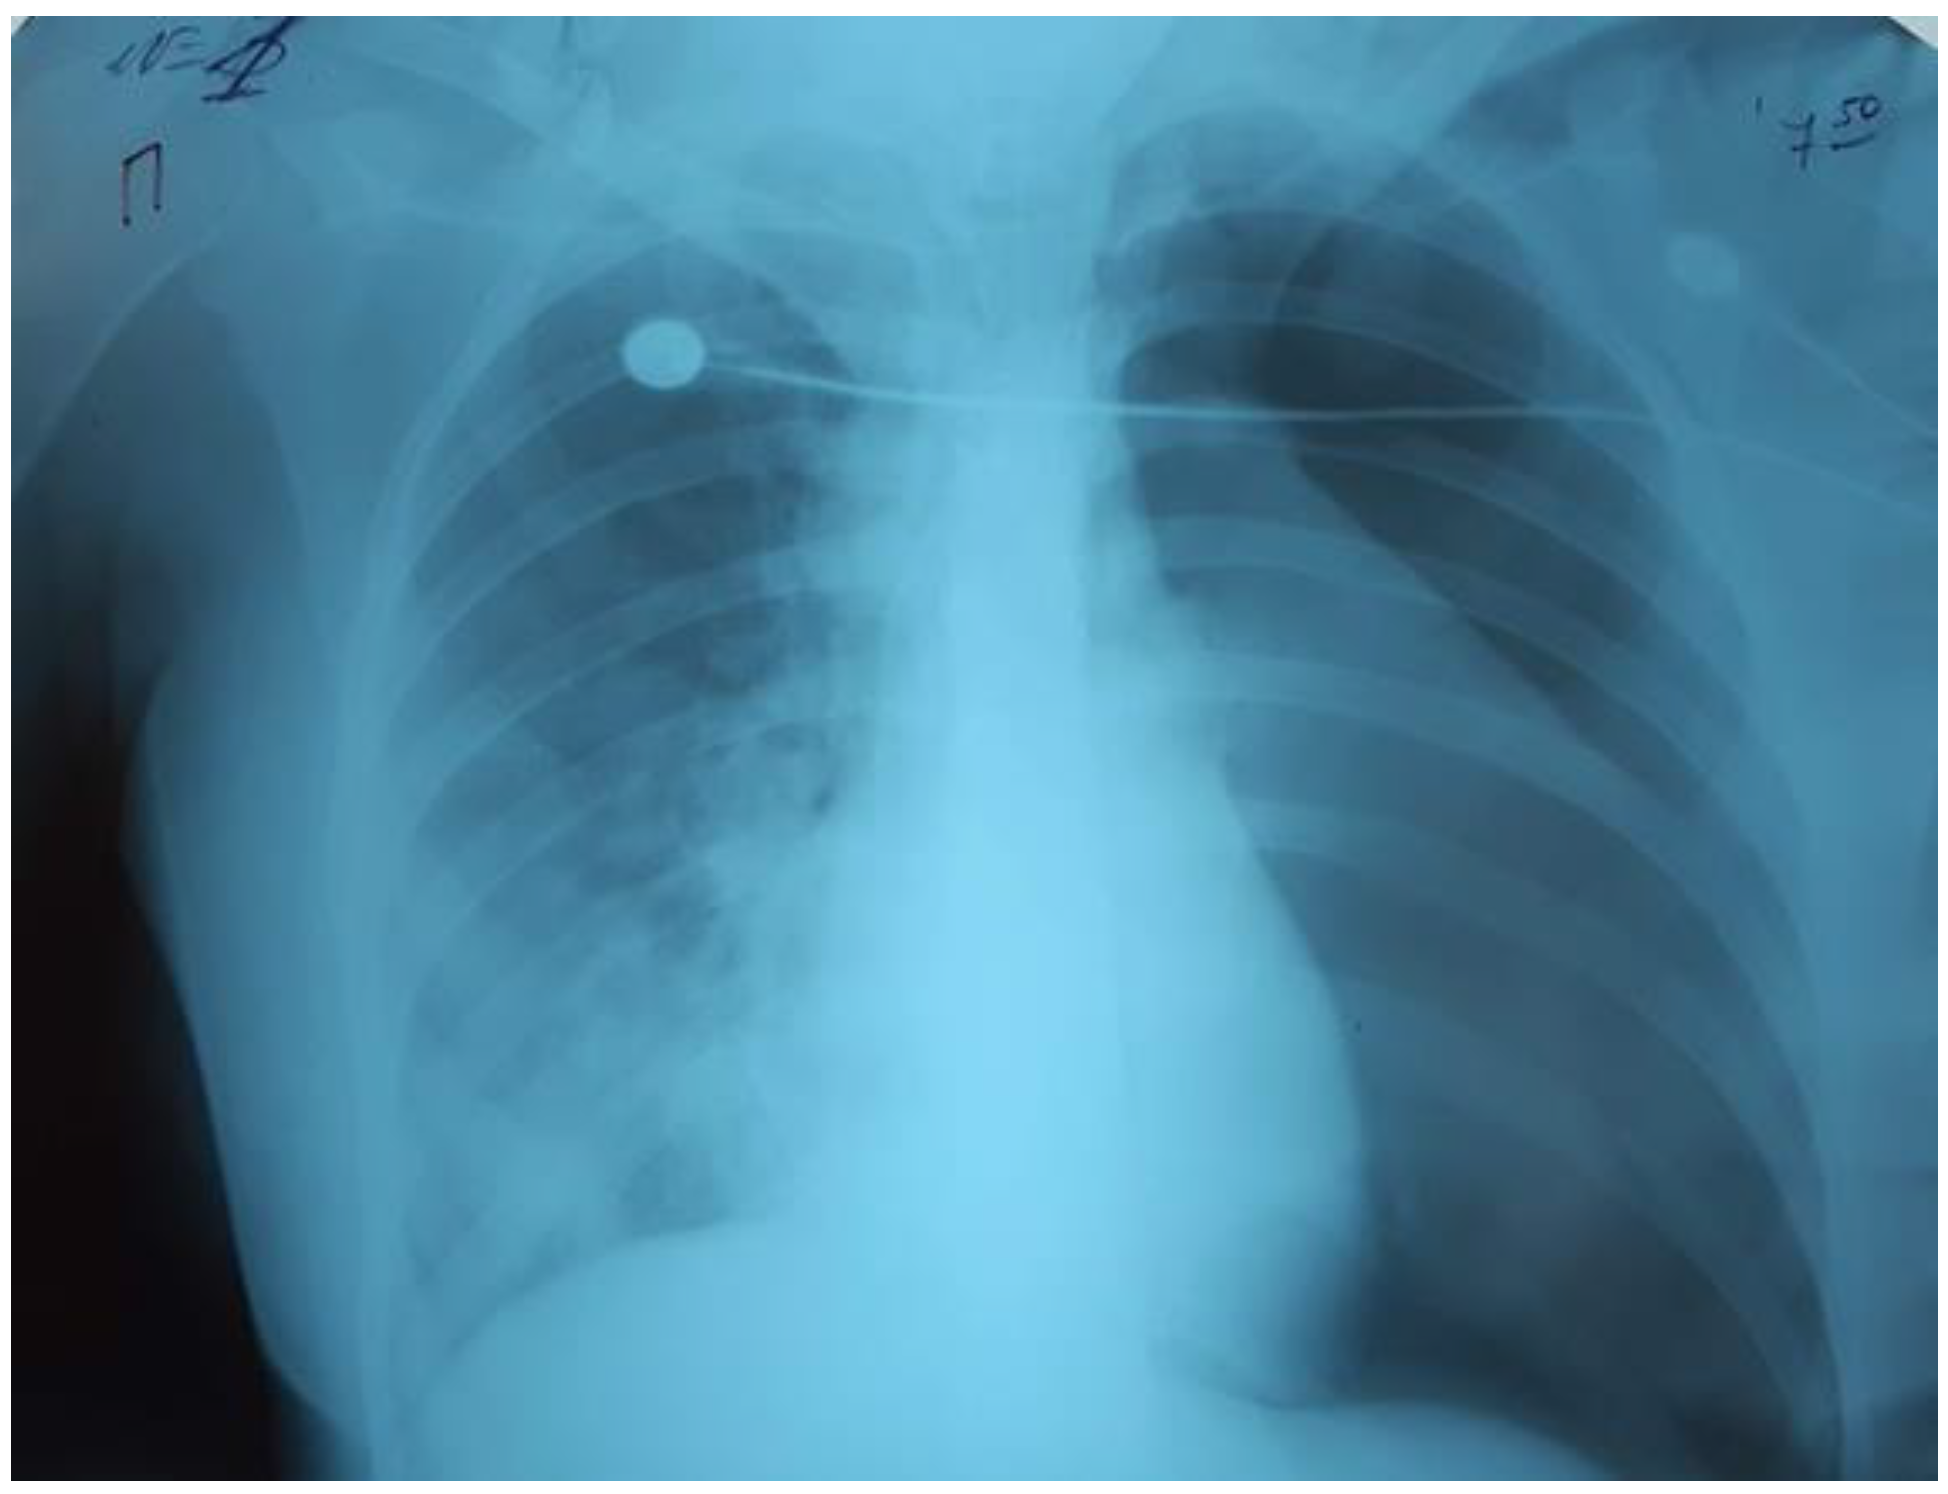

On the third day of mechanical ventilation, the girl had a complication—left-sided pneumothorax. The urgent drainage of the pleural cavity (Figure 4) was performed, as well as reduction of mechanical ventilation parameters: P/SIMV, FiO2 80%, PIP 12 cmH2O, PEEP 8 cmH2O, I/E 1-1.5, TV 300 mL/kg.

Figure 4.

Left-sided pneumothorax.

Over the next 24 hours, there was a progressive decrease in oxygenation: PaO2/FiO281, PaO2 80 mmHg, PaCO2 61 mmHg. The chest radiograph showed that the left lung was partly collapsed; there was an active air discharge through the drainage. The drainage of the left pleural cavity and the second drainage were performed (Figure 5).

Figure 5.

The left lung was partly collapsed.